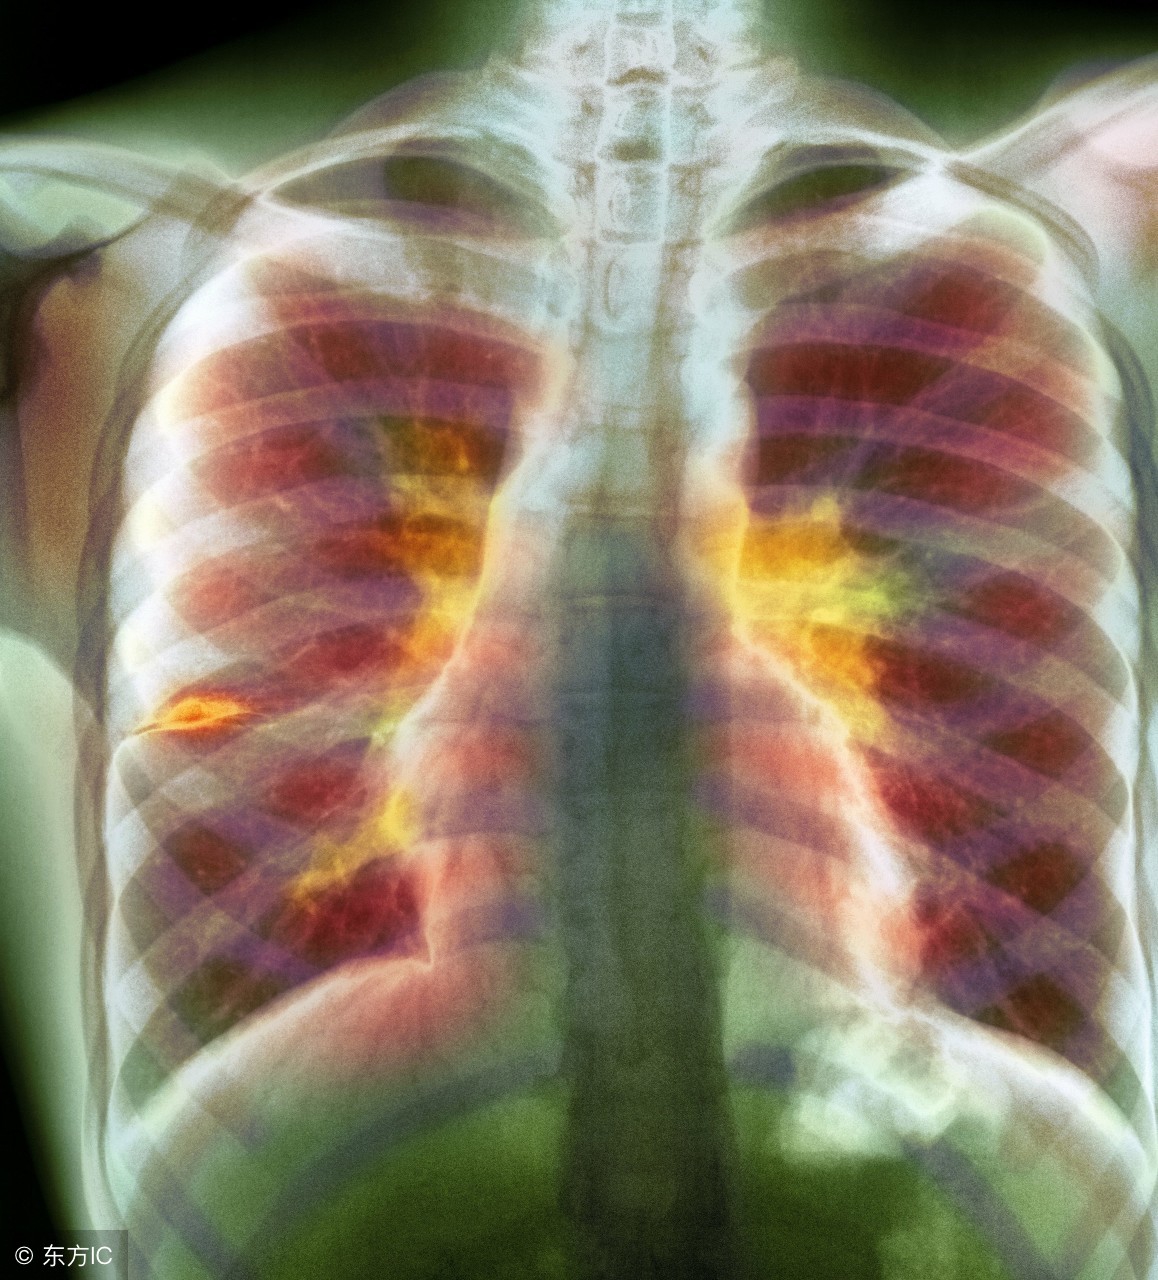

肺结核大家应该都听说过,但是肺结核吃什么依旧是一个疑问。大家都知道肺结核是由于病菌引起的疾病,治疗所花费的时间较为长,那么就需要配和日常的饮食啦。那么肺结核患者应该吃什么呢?下面告诉你,肺结核患者的饮食宜忌。